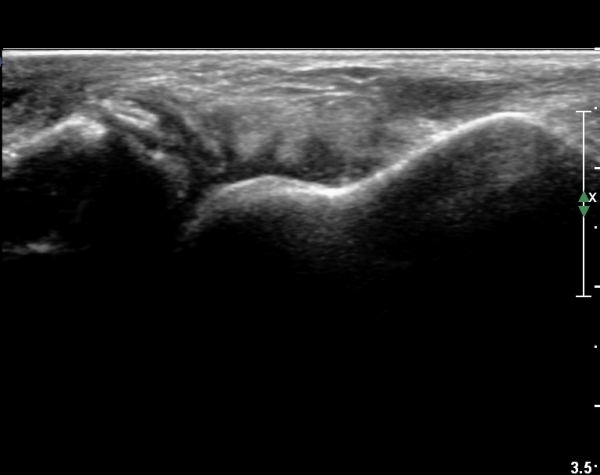

Á¾°ñºñ°ñÀδë Á¾´Ü¸é°Ë»ç¿¡¼­ ÀδëÀÇ ºñ°ñºÎÂøºÎ Àú¿¡ÄÚ ºÎÁ¾°ú ºñ°ñÀÇ °ß¿­°ñÀýÀÌ °üÂûµÈ´Ù(»çÁø 5, 6, 7).

Á¾°ñºñ°ñÀÎ´ë ºÎÇϰ˻翡¼­ Á¾°ñÀÇ °úµµÇÑ ¿òÁ÷ÀÓÀÌ °üÂûµÈ´Ù(÷ºÎµ¿¿µ»ó 3, 4).

ºÎÇÏ°Ë»ç °á°ú·Î º¼ ¶§ ÀδëÀÇ ºÎºÐÆÄ¿­·Î ÆÇ´ÜµÈ´Ù.